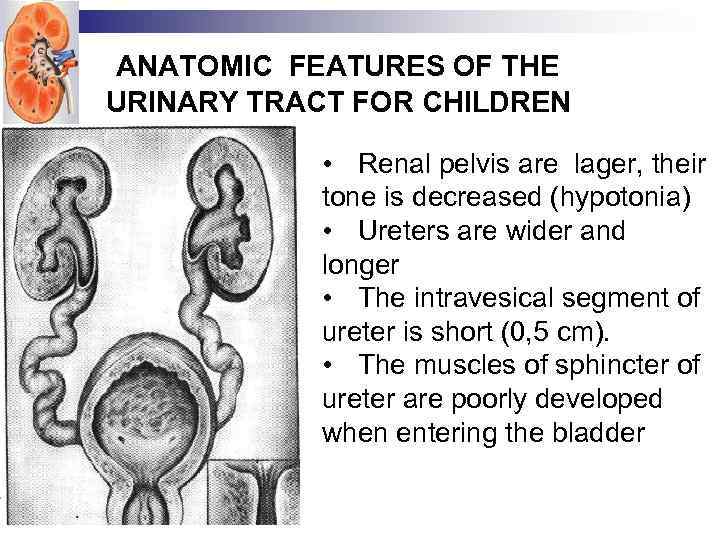

ANATOMIC FEATURES OF THE URINARY TRACT FOR CHILDREN • Renal pelvis are lager, their tone is decreased (hypotonia) • Ureters are wider and longer • The intravesical segment of ureter is short (0, 5 cm). • The muscles of sphincter of ureter are poorly developed when entering the bladder

ANATOMIC FEATURES OF THE URINARY TRACT FOR CHILDREN • Renal pelvis are lager, their tone is decreased (hypotonia) • Ureters are wider and longer • The intravesical segment of ureter is short (0, 5 cm). • The muscles of sphincter of ureter are poorly developed when entering the bladder